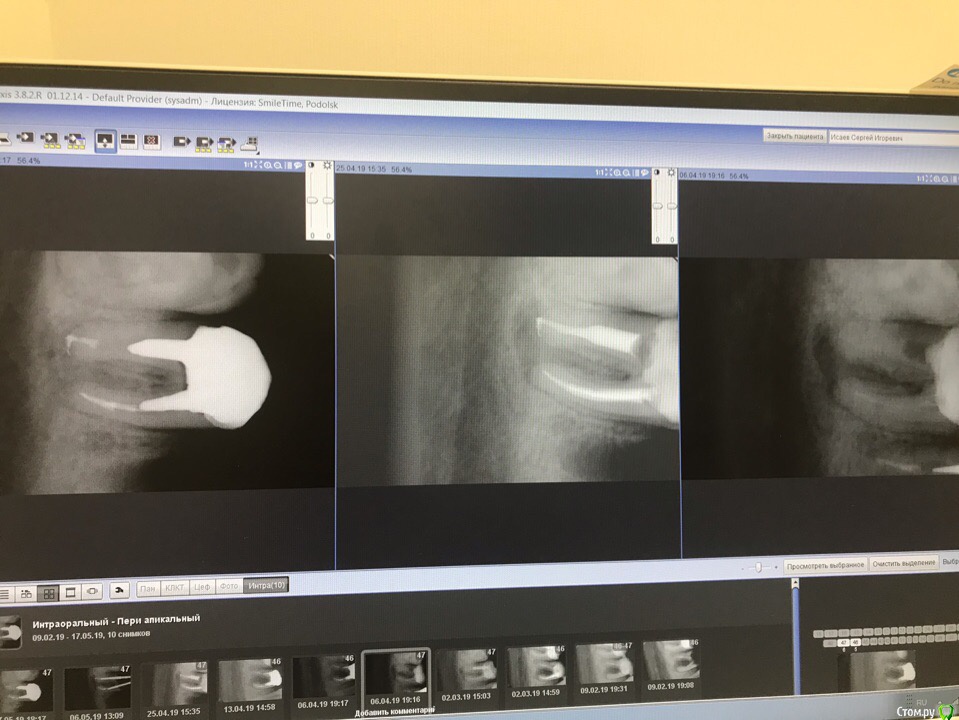

1586Doc Опубликовано 30 марта, 2019 Автор Поделиться Опубликовано 30 марта, 2019 (изменено) Еще немного работы45 зуб эндо и пломба и 46 зуб эндо и пломба на снимке справа Изменено 30 марта, 2019 пользователем 1586Doc Ссылка на комментарий